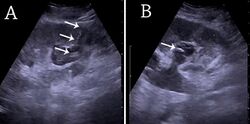

The kidney is divided into parenchyma and renal sinus. The renal sinus is hyperechoic and is composed of calyces, the renal pelvis, fat and the major intrarenal vessels. In the normal kidney, the urinary collecting system in the renal sinus is not visible, but it creates a heteroechoic appearance with the interposed fat and vessels. The parenchyma is more hypoechoic and homogenous and is divided into the outermost cortex and the innermost and slightly less echogenic medullary pyramids. Between the pyramids are the cortical infoldings, called columns of Bertin (Figure 1). In the pediatric patient, it is easier to differentiate the hypoechoic medullar pyramids from the more echogenic peripheral zone of the cortex in the parenchyma rim, as well as the columns of Bertin (Figure 2).[1]

Figure 2. Normal pediatric kidney. * Column of Bertin; ** pyramid; *** cortex; **** sinus.[1]